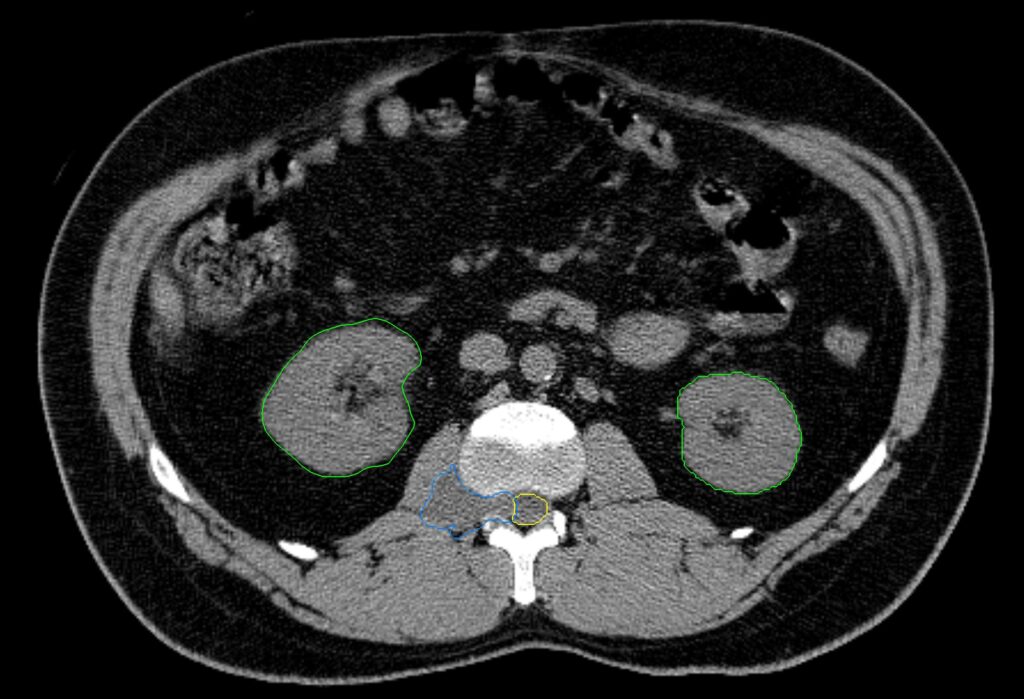

Adrenal Metastasis

< View All Plan Studies CYBERKNIFE SYSTEM Adrenal Metastasis of Right Kidney Cancer Case History AGE: 81-year-oldGENDER: Female Diagnosis: Oligometastasis in the left adrenal gland, following surgery for right kidney cancer, now with secondary metastasis Planning CT Images Treatment Plan Images Treatment Planning Highlights Fractionation 45 Gy in 3 fractions PTV(s) Volume PTV, 14.7 cc […]